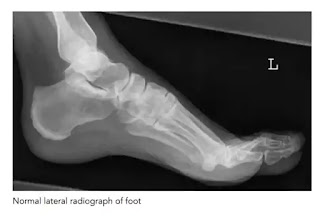

3. Foot lateral view

यह projection dorsi plantar projection के अथवा में foreign body के location को check करने के लिए किया जाता है। tarsal bones के fracture या dislocation तथा base of metatarsal fracture या dislocation को देखने में भी इस projection का प्रयोग किया जाता है।Position of patient and cassette

Foot के lateral aspect को cassette के contact में लाने के लिए पैर को dorsi plantar position से बाहर की ओर rotate करते हैं। support प्रदान करने के लिए knee के नीचे pad लगा देते हैं । foot की position को थोड़ा सा इस प्रकार adjust करते हैं जिससे कि foot की plantar surface cassette के लम्बवत हो जाए ।Direction and centring of the x-ray beam

Verical central ray को सीधा navicular cuneiform joint के ऊपर देते हैं।Essential image characteristics

यदि किसी संदिग्ध foreign body की जांच हो रही हो तो पर्याप्त kvp को select करना चाहिए । जिससे कि soft tissue की structure की तुलना में foreign body दिखाई दे सके।Note-: puncture स्थान पर metal marker को सामान्यतः foreign body की स्थिति को पता लगाने के लिए इस्तेमाल करते हैं।